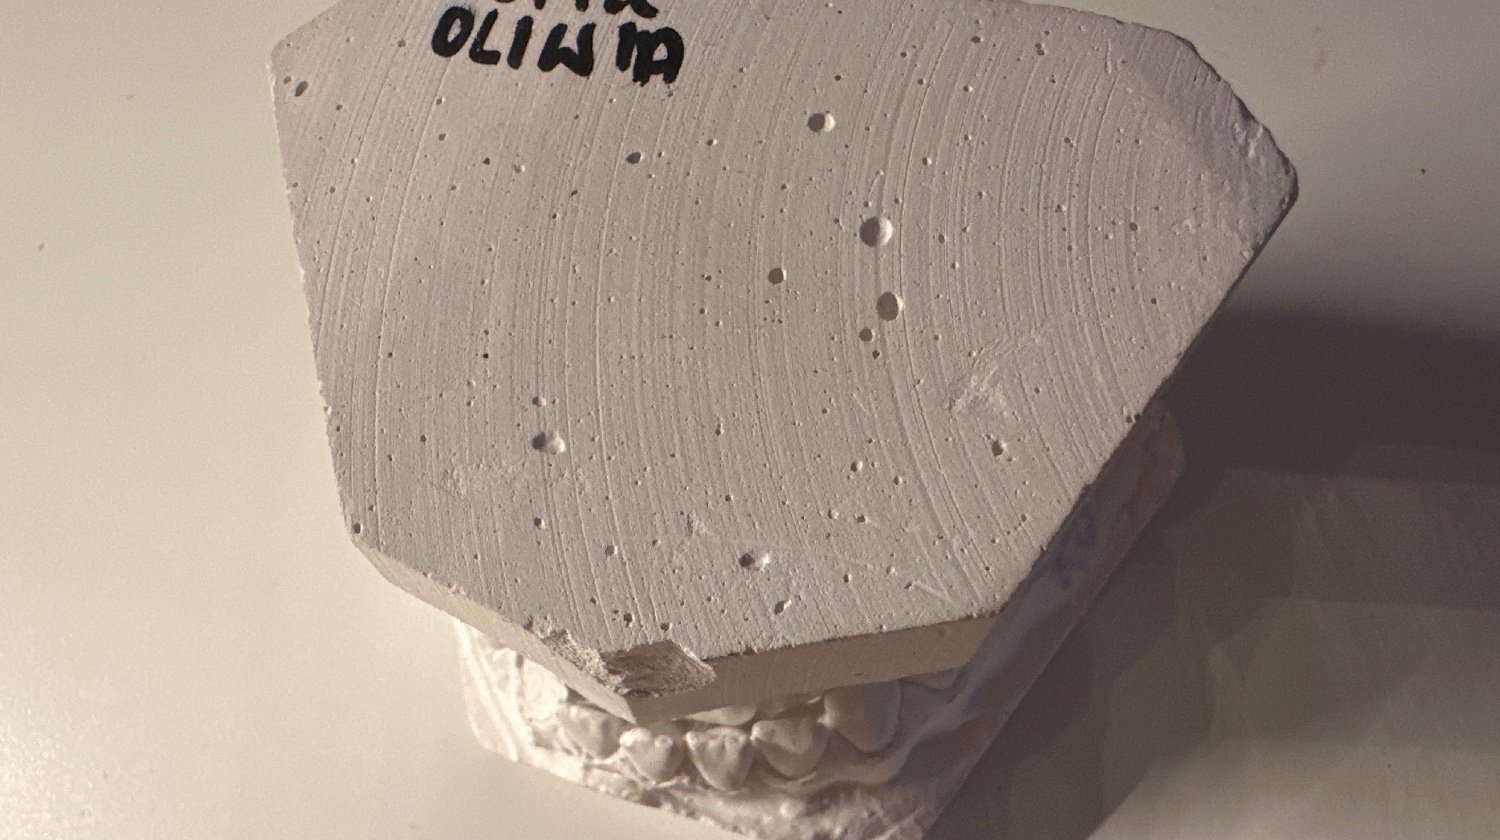

Mój aktualny stan zgryzu przed założeniem aparatu

Jestem aktualnie w trakcie zmiany ortodonty, który ma mnie przygotować do operacji. W pierwszej kolejności muszę wykonać badania, prześwietlenia takie jak np. pantonogram. Na zdjęciu zrzutki widnieje moje prześwietlenie z 2023 oraz 2021 roku. Przed i po usunięciu 8 do aparatu, którego założenie nigdy nie nastało. Niestety z czasem ulega ono przeterminowaniu i należy wykonać nowe. Jestem pod opieką ortodonty od już prawie 5 lat. Moje leczenie nie postępuje przez liczne przeszkody takie jak brak funduszy, problemy z ustaleniem operacji (w moim mieście tylko jeden chirurg operuje, który z dnia na dzień przestał operować) itp.

Po wykonaniu takiego zdjęcia należy zrobić wycisk zębów (stary wycisk widoczny na zdjęciach zrzutki), a następnie skonsultować plan leczenia z chirurgiem oraz ortodontą. W moim przypadku będzie to skrócenie i naprostowanie żuchwy oraz segmentacja górnej szczęki. Po jasnej decyzji chirurga ortodonta może założyć aparat, aby upośledzić zgryz (zgryz musi zostać upośledzony jeszcze bardziej, aby po operacji mógł zostać złożony prawidłowo). W między czasie dochodzą dodatkowe badania kontrolne wyciski, zdjęcia itp. Po ułożeniu zębów do operacji wyznaczany jest jej termin. Tutaj operacja jest na NFZ, jednak płytki do złączenia kości są już nie refundowane, a są one niezbędne. Jeśli wszystko po operacji dobrze pójdzie, pozostaje rekonwalescencja, konsultacje, badania kontrolne i rehabilitacja stawów. Po operacji noszenie aparatu może trwać jeszcze do 2 lat